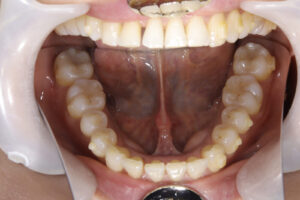

Invisalign correction failure

orthodontic treatment

表側矯正での再治療

治療方針

インビザラインと歯周病の相性はよくありません。

それは、インビザラインの着脱で歯が揺り動かされる事とアタッチメントの下は磨けないからです。

そのため、歯周病を悪化させる方向になってしまいます。

歯周病治療の場合、表側のワイヤー矯正をお勧めします。

それは、まだ歯磨きがやりやすい矯正になるからです。